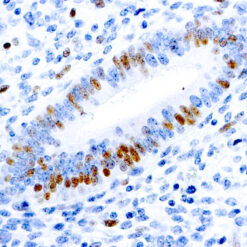

This antibody recognizes insoluble elastin, α-elastin, soluble non-cross linked precursor of elastin (tropoelastin). Elastin is an important polymeric protein of connective tissue that imparts elasticity to vertebrate elastic tissues.

| Clone | BA-4 |

| Immunogen | Bovine α-elastin |

| Positive Control Tissue | Heart, Kidney |